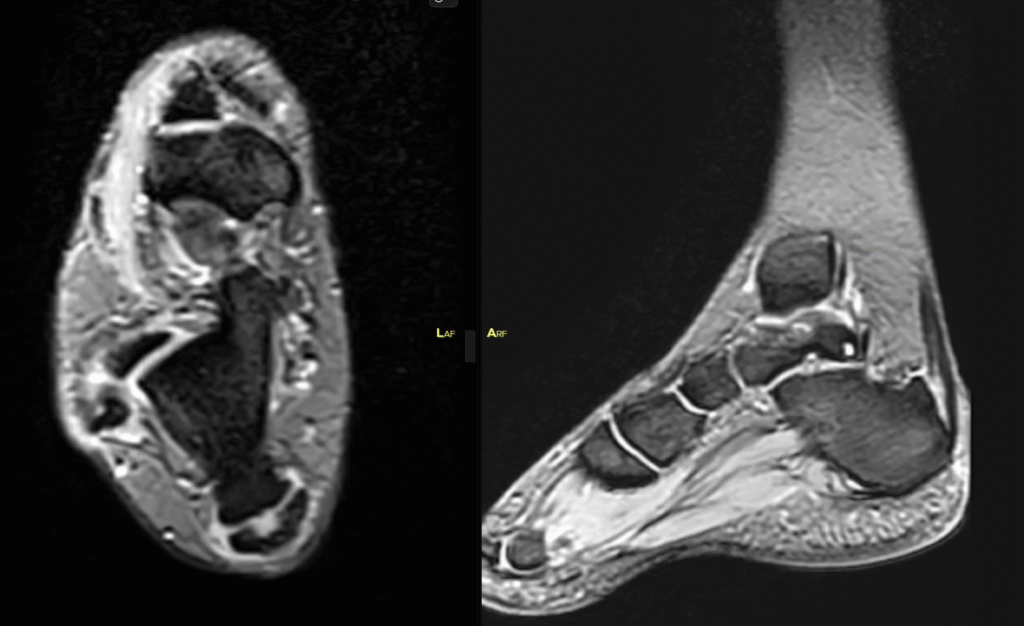

- MR ve BT:

- Aşil tendon insersiyonunda tendinopati

- Retrocalcaneal bursit

- Haglund deformitesi teyit edildi.

Preoperatif MRG ve röntgenler